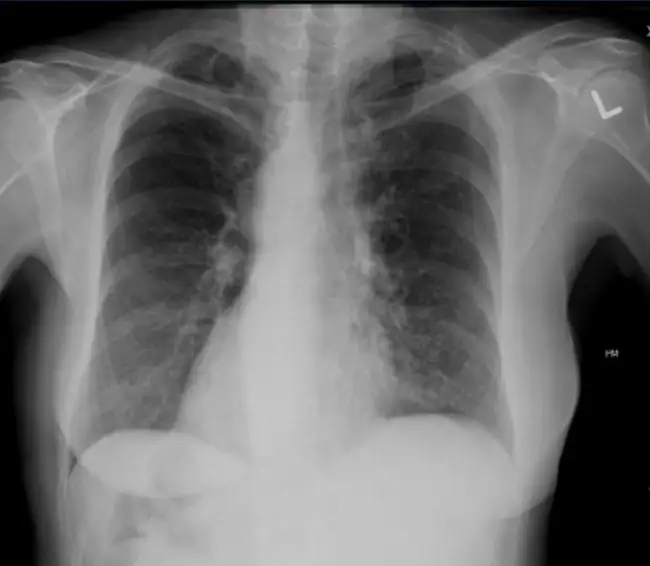

A 45-year-old woman presents to urgent care with a persistent productive cough for the past few months. Over the past week, she has noticed more sputum production, which is thick and dark in color, as well as fatigue and dyspnea on exertion. She denies fevers, pharyngitis, abdominal pain, or gastrointestinal upset. She denies tobacco use or occupational exposures to any inhaled chemicals. Physical exam reveals that the patient is afebrile with vital signs within normal limits. Coarse inspiratory and expiratory rales are heard in bilateral bases of lungs.

View the chest x-ray image and consider what your diagnosis and next steps would be. Resolution of the case is described on the following page.